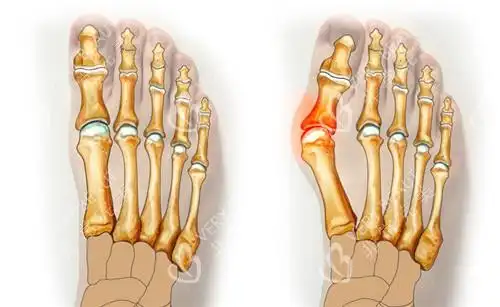

正常脚与大脚骨的区别,张树伟介绍

拇趾向外偏斜,拇趾近节趾骨与第1跖骨成角大于15°,有"大脚骨","大觚